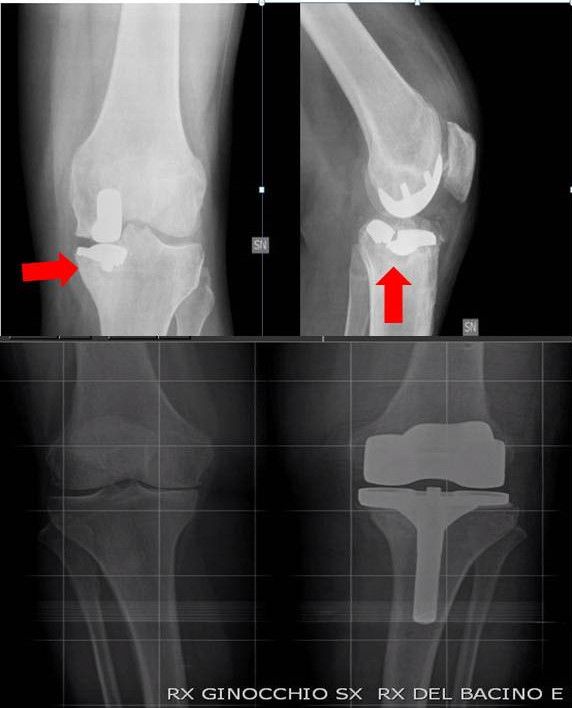

Dal 1999, abbiamo effettuato 1500 interventi di protesi di ginocchio computer assistita. In questo studio abbiamo valutato 22 interventi consecutivi di revisione di UKR computer assistita (gruppo A). In tutti questi casi la diagnosi era di mobilizzazione asettica o impianto protesico doloroso. Nessun caso di franca o sospetta sepsi è stato incluso. La navigazione è stata utilizzata per aiutare il chirurgo nella valutazione dell’asse dell’arto inferiore, nei tagli ossei e nel bilanciamento legamentoso. Dopo un follow-up minimo di 12 mesi, tutti i pazienti sono stati comparati, con successo, a pazienti che erano stati sottoposti ad intervento di revisione di UKR, nel nostro ospedale, utilizzando le tradizionali guide di allineamento extramidollare (gruppo B). Ogni paziente è stato abbinato per sesso, età, diagnosi preoperatoria, e perdita ossea intraoperatoria secondo la classificazione dei difetti ossei dell’ Anderson Orthopedic Research Institute. I pazienti sono stati abbinati con una differenza di età massima di tre anni. Nel gruppo A, gli interventi di revisione sono stati eseguiti utilizzando un sistema di allinemaneto computer assistito Tac-free (OrthoPilot 4.08, 4.2, e 4.3; Aesculap, Tullingen, Germany).

Nel gruppo A, l’intervento di revisione è stato eseguito utilizzando nuovamente una UKR in 2 casi, una Bi-UKR in 1 caso, a protesi totale a risparmio del crociato (CR) in 7 casi e una protesi totale postero stabilizzata (PS) in 12 casi. Nel gruppo B invece, l’intervento di revisione è stato eseguito utilizzando una CR TKR in 5 casi, una PS TKR in 14 casi e una CCK TKR in 3 casi. Abbiamo utilizzato un augmentation in metallo di 4 mm in 3 casi nel gruppo A, mentre nel gruppo B abbiamo utlizzato 5 augmentation in metallo di 4 mm e 1 da 8 mm. Inoltre in 2 casi nel gruppo B è stato utilizzato osso di banca. Nel gruppo A sono stati utilizzati due steli tibiali non cementati da 80 mm, mentre nel gruppo B sono stati utilizzati 2 steli tibiali non cementati da 80 mm e 3 da 120 mm.

All’ ulitmo follow-up, l’ angolo HKA medio è stato di 179,4° (range 177°-181°) nel gruppo con sistema di navigazione e 178,1° (range 175°-182°) nel gruppo con strumentario classico, senza differenze statisticamente significative. Tutte le protesi re-impiantate col sistema di navigazione sono state posizionate entro 3° dai 180° ideali dell’angolo HKA prefissato. Il ripristino della joint line è stato calcolato su 20 pazienti del gruppo A e su 19 del gruppo B; 2 casi del gruppo A e 3 casi del gruppo B sono stati esclusi poiché già sottoposti a TKR nell’arto contro laterale. All’ ultimo follow up il ripristino della joint line è stato maggiormente ottenuto nel gruppo A con significatività statistica rispetto al gruppo B, con un valore medio statisticamente più vicino a 0 mm (Tabella 2).